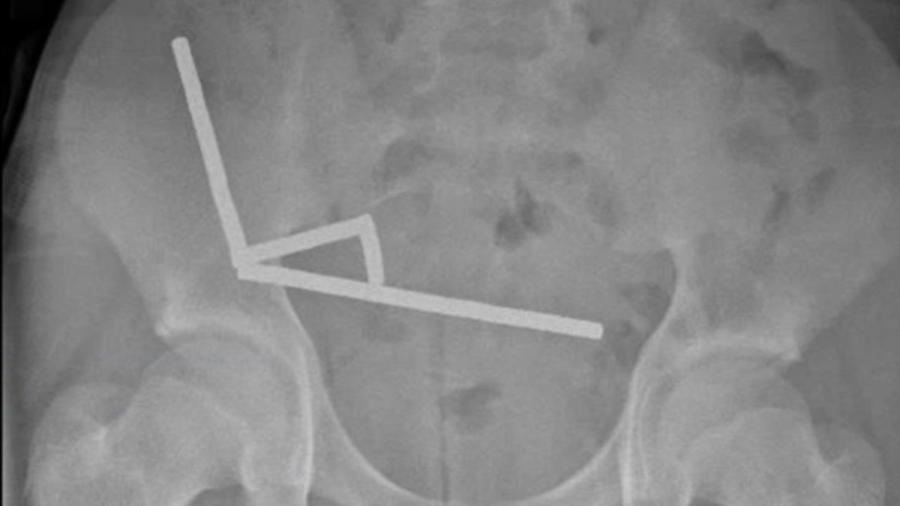

Рентгеновите снимки показали четири линейни вериги от магнити в отделни участъци на червата.

Тъй като магнитите се привличали един към друг през тъканите, това довело до притискане и прекъсване на кръвоснабдяването, което причинява тъканна некроза (умиране на тъкан).